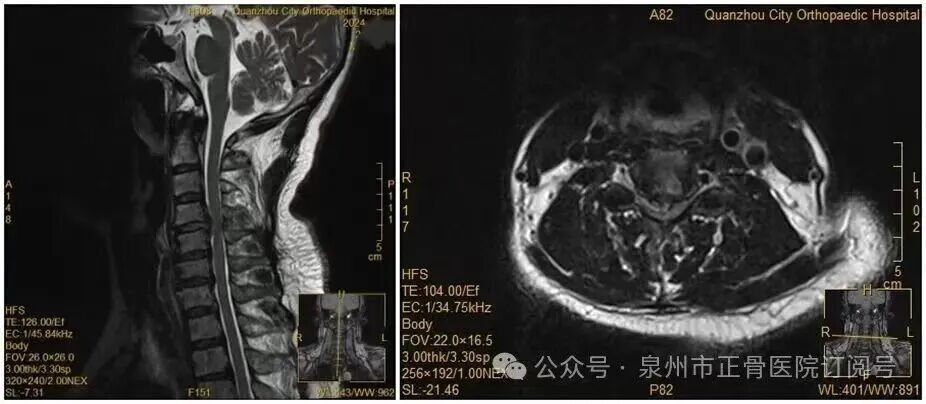

翻个身,手突然动不了了 低头玩手机,发现下肢无法动弹 50岁的王女士、19岁的学生阿东 分别经历了这种“飞来横祸” 罪魁祸首竟都和颈椎病有关 ↓↓↓ 事件回顾: 50岁女子夜里翻手机 双手突然失去知觉,确诊瘫痪 近日,福建省泉州市50岁的王女士因反复手麻、酸痛前往泉州市正骨医院就诊,被确诊为颈椎间盘突出症。医生介绍,她的颈椎间盘已经巨大脱出,完全符合手术指征,建议尽快手术干预。但王女士心存顾虑,坚持选择保守治疗。 没想到会诊当晚,王女士翻身拿手机的瞬间,双手突然失去知觉。经医院检查,其关键肌肌力已降至1级或0级,确诊为瘫痪。 王女士术前MRI。图片来源:泉州市正骨医院 医生推测,王女士翻身时,脱出的椎间盘突然进一步卡压到脊髓神经,引发了急性症状。幸运的是,王女士接受手术后,她的肢体功能正在逐渐恢复正常。 无独有偶,阿东是某大学大三学生,暑假期间,他在一家餐饮店打工,每天连续低头洗碗、擦桌子4小时以上,回宿舍后,他又趴在床上玩手机2至3小时。 事发前几天,阿东感到身体异常,手脚及颈后背常有麻木疼痛感。随后的几天,他的麻木感加剧,甚至出现双下肢无法动弹,他迅速拨打120。 经检查,医生发现阿东颈椎C4-T1椎管内存在巨大占位性病变,压迫脊髓,为挽救这名年轻小伙的行动能力,医院紧急为他手术治疗。 医生推测,可能是阿东的椎管内硬膜外小血管存在异常,如血管畸形等,在长期低头工作等外因作用下,使血管破裂出血,形成血肿,导致压迫脊髓。术后,阿东的肢体瘫痪症状有所缓解。 科普时间: 低头玩手机 会让颈椎承受27公斤重压 颈椎间盘突出症虽然常见,但千万别忽视它的严重性。医生表示,尤其是颈椎间盘脱出症,是颈椎间盘突出中较为严重的类型,影像可见颈椎间盘的髓核突破纤维环,压迫周围组织。 该病常见症状包括颈部疼痛僵硬、上肢放射性疼痛,若不及时干预,脱出的髓核会持续压迫神经根、脊髓,可能造成不可逆的脊髓神经损伤,甚至瘫痪。 调查显示,我国20至40岁青壮年颈椎病患病率高达59.1%。世界卫生组织已将颈椎病列为“全球十大顽症”中的第二位,发病率高达17.6%。 研究显示,低头玩手机,会让颈椎承受27公斤的重压,比一个7岁小孩还重。 据了解,颈椎病的发生与患者职业紧密相关,如会计、办公室人员等,发病率明显高于其他人群。长时间使用笔记本电脑、低头玩手机人群的发病率也高于其他人群。 仁济医院提醒: 警惕“痛、麻、乏” 颈椎病的3个信号 上海交通大学医学院附属仁济医院提醒,颈椎病并不难发现,日常要警惕“痛、麻、乏”三大症状↓↓ 痛:颈背部、肩膀和手臂疼痛 当有颈椎间盘突出或者有急性外伤的情况下,患者就会产生疼痛,且常在双手下垂时疼痛加重,不少患者举着胳膊前来就诊。 麻:双手、双足麻 当颈椎间盘突出到了一定的程度,压迫了神经,神经会出现传导阻滞了便产生麻,这种麻木往往会严重影响日常生活工作,比如无法完成一些精细动作,双脚走路绵软无力等。 乏:双手臂、双腿没有力气 最常表现为双手拧毛巾没有力气,或者双腿不听使唤,走路打漂不稳伴有踩棉花感。 如果出现了上述症状 先不要紧张 教大家3招轻松应对 ↓↓↓ 及时纠正改善生活习惯 改善工作中的不良习惯性体位,伏案工作不应连续超过1小时,定期活动头颈部,以放松颈椎。 睡觉枕头不宜过高 睡觉时枕头不宜过高,以符合颈椎生理曲度为宜,尽量枕在脖子后方。 要保证适当的锻炼 如将双手十字合拢交叉,将其举过头顶置于枕颈部,之后将头后仰,双手逐渐用力向头方向牵引5至10秒钟,如此连续3至4次即可起到缓解椎间隙压力的作用。 在各种运动中最好的是游泳,游泳时颈椎不会受到重力的影响,而且锻炼了颈部的肌肉,长期坚持可以治愈轻度的颈椎间盘突出。 快来测测看 你的颈椎如何? 日常生活中要保护好颈椎 注意劳逸结合 养成良好睡姿 保持正确的体态 快转发提醒身边人吧~